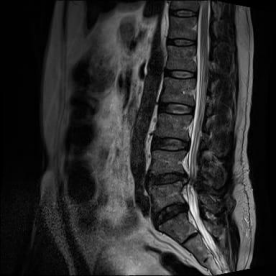

No pós-operatório imediato, o paciente relatou dor lombar de alta intensidade, controlada apenas com o uso de opioides. No segundo dia de pós-operatório, o paciente conseguiu deambular e houve melhora clínica significativa, com redução da dor e progresso na deambulação e ortostatismo prolongado. O paciente recebeu alta três dias após a cirurgia e foi prescrita apenas medicação sintomática para dor neuropática, como pregabalina e analgésicos, além de iniciar fisioterapia motora. A RM de controle demonstrou artrodese posterior fixando o segmento de L4-L5, com hastes e parafusos metálicos intrassomáticos e transpediculares, presença de CAGE no espaço intervertebral de L4-L5, edema ósseo nos platôs vertebrais contiguos de L4-L5, que pode estar relacionado a alterações degenerativas do tipo Modic I, discopatia inicial em L5-S1, com abaulamento discal, sem conflito radicular. Dessa forma, a cirurgia foi bem-sucedida, com recuperação estrutural adequada.

Figura 5 e 6. RM de coluna lombossacra (sequências T2 ponderadas, planos sagital e axial) demonstrando degeneração discal difusa, com redução da altura e do sinal em T2 dos discos intervertebrais. Nota-se protrusão posterior do disco L5-S1, determinando compressão do saco dural e contato com a raiz nervosa correspondente.